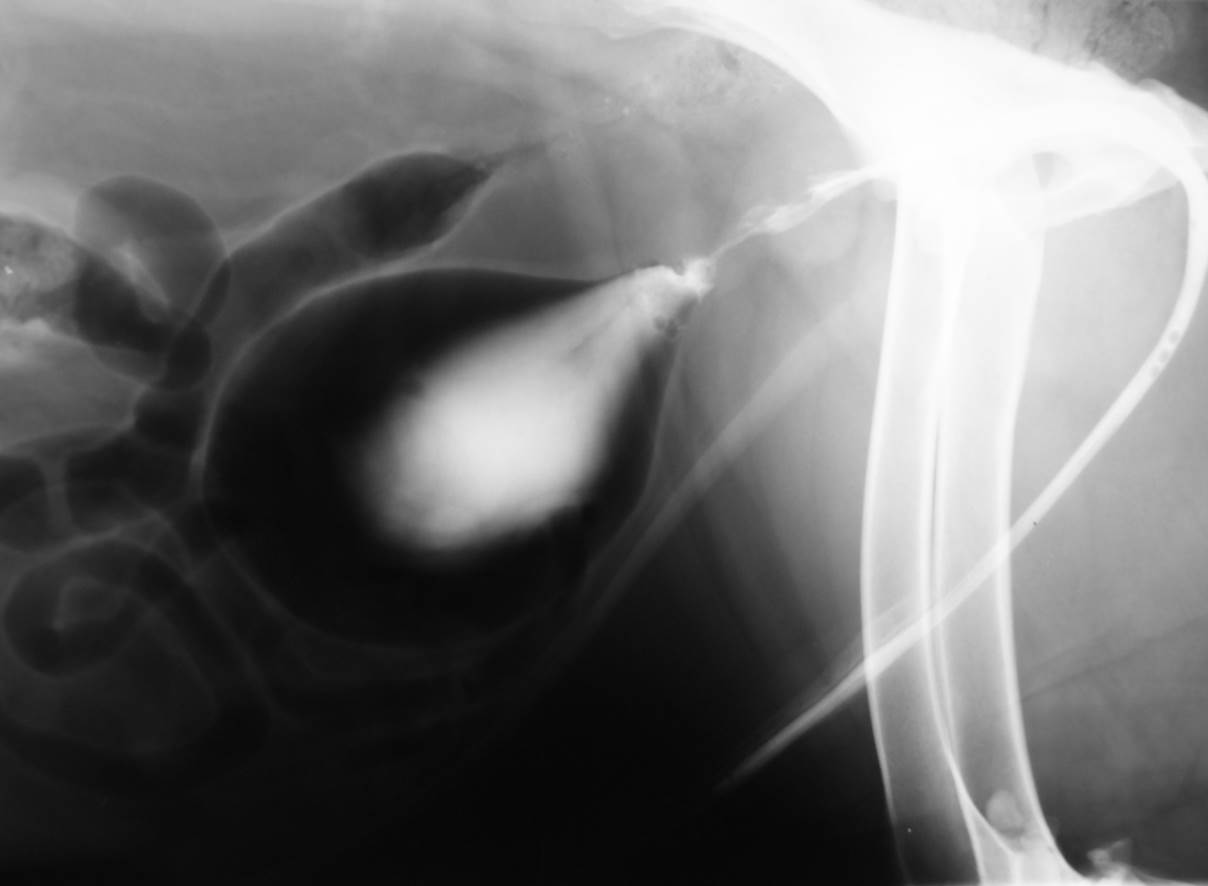

Case Chewbacca

Discuss this case?

–visible on the lateral and VD views

–visible at different time points during the study